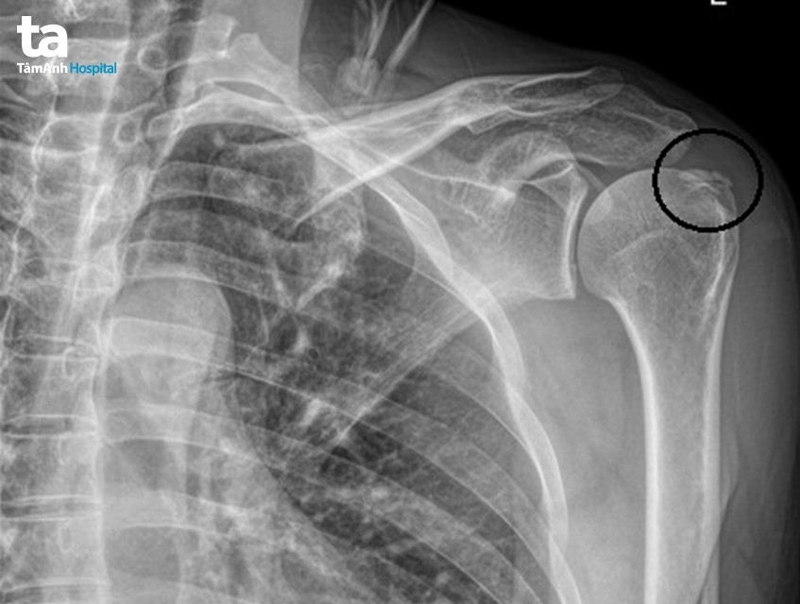

Khi đến bệnh viện, bác sĩ sẽ thực hiện một số biện pháp kiểm tra như là chụp X quang để xác định vị trí xương gãy, mức độ trật khớp (nếu có).

Đặc biệt, trường hợp trật khớp vai kèm theo gãy xương, bác sĩ sẽ chỉ định thực hiện kết hợp phương pháp chụp CT scan để tăng độ chính xác cho kết quả chẩn đoán. Ngược lại, nếu tình trạng trật khớp đơn thuần không bị gãy xương, bạn có thể được điều trị bằng những biện pháp không xâm lấn khác như nắn khớp, cố định vai hay sử dụng thuốc giảm đau, thuốc giãn cơ.

Chụp X-quang trật khớp vai Bị trật khớp vai khi ngủ là tình trạng tương đối phổ biến. Mặc dù không quá nguy hiểm nhưng nếu không chữa trị kịp thời có thể dẫn đến nhiều biến chứng khó lường. Vì vậy hãy lập tức đến gặp bác sĩ nếu nhận thấy tình trạng của mình có nhiều chuyển biến bất thường nhé!